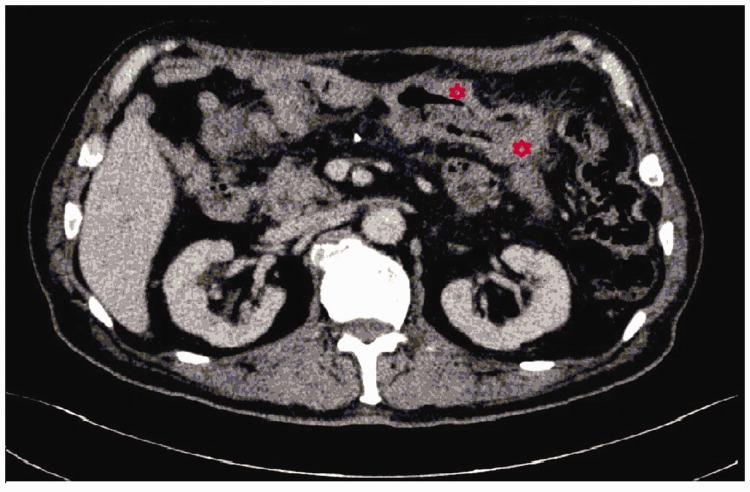

Primary colonic lymphoma is a very rare malignant tumor with no standard treatment. We report two cases of primary colonic lymphoma successfully treated with surgery and chemotherapy, and chemotherapy alone, respectively. The first case was a 61-year-old woman who presented with abdominal pain of more than 1 month. The patient was diagnosed with a colonic tumor, and immunohistochemical examinations confirmed the initial diagnosis of colonic lymphoma. The patient underwent laparoscopic-assisted right hemicolectomy followed by postoperative adjuvant chemotherapy with the cyclophosphamide, doxorubicin, vincristine, and prednisone (CHOP) regimen, combined with targeted therapy with rituximab (R-CHOP). The second case was a 78-year-old man who presented with a complaint of abdominal distention for more than 1 year. Diffuse large B-cell lymphoma was definitively diagnosed by immunohistochemical examinations, and the patient underwent systemic chemotherapy with the R-CHOP regimen. Primary colonic lymphoma is a rare type of non-Hodgkin's lymphoma (NHL), and the clinical treatment is not standardized, unlike for many other types of lymphoma. Therefore, treatment is mainly based on the patient's symptoms to determine whether surgery or systemic chemotherapy is appropriate. Rituximab is effective in some patients and may play an important role in the treatment of unresectable or asymptomatic colonic lymphoma.

原发性结肠淋巴瘤是一种非常罕见的恶性肿瘤,目前尚无标准的治疗方法。我们报告了两例成功接受手术和化疗以及单纯化疗治疗的原发性结肠淋巴瘤病例。第一例为 61 岁女性,因腹痛 1 个月余就诊。患者被诊断为结肠肿瘤,免疫组化检查明确为结肠淋巴瘤的初步诊断。患者接受了腹腔镜辅助右半结肠切除术,术后采用环磷酰胺、多柔比星、长春新碱和泼尼松(CHOP)方案辅助化疗,并联合利妥昔单抗(R-CHOP)进行靶向治疗。第二例为 78 岁男性,因腹胀 1 年余就诊。免疫组化检查明确诊断为弥漫性大 B 细胞淋巴瘤,患者接受了 R-CHOP 方案的全身化疗。原发性结肠淋巴瘤是一种罕见的非霍奇金淋巴瘤(NHL),其临床治疗方法不规范,与许多其他类型的淋巴瘤不同。因此,治疗主要根据患者的症状来确定是否适合手术或全身化疗。利妥昔单抗对一些患者有效,可能在治疗不可切除或无症状的结肠淋巴瘤中发挥重要作用。